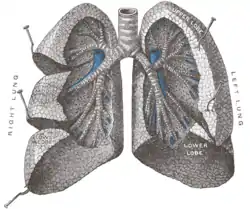

Respiration

Respiration is the physical process of gas exchange between an organism and its environment involving four steps (ventilation, distribution, perfusion and diffusion) and two processes (inspiration and expiration). Respiration can be described as the mechanical process of air flowing into and out of the lungs on the principle of Boyle's law, stating that, as the volume of a container increases, the air pressure will decrease. This relatively negative pressure will cause air to enter the container until the pressure is equalized. During inspiration of air, the diaphragm contracts and the lungs expand drawn by pleurae through surface tension and negative pressure. When the lungs expand, air pressure becomes negative compared to atmospheric pressure and air will flow from the area of higher pressure to fill the lungs. Forced inspiration for speech uses accessory muscles to elevate the rib cage and enlarge the thoracic cavity in the vertical and lateral dimensions. During forced expiration for speech, muscles of the trunk and abdomen reduce the size of the thoracic cavity by compressing the abdomen or pulling the rib cage down forcing air out of the lungs.